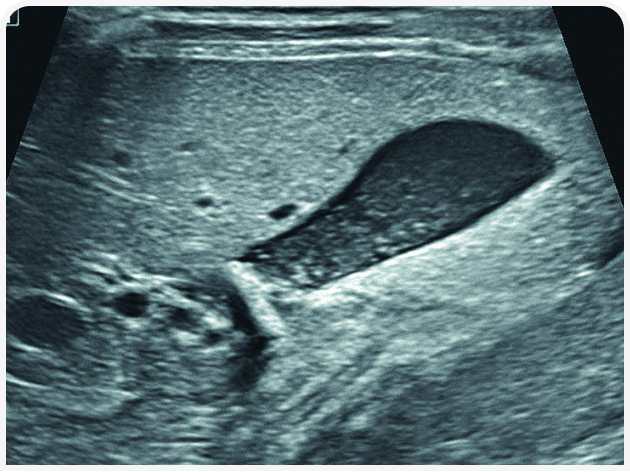

Решающее значение для диагностики и лечения в этом случае будет иметь ультразвуковое исследование органов брюшной полости (Рисунок 6). Диагностику триадита у кошек облегчают визуализация поджелудочной железы и определение толщины/архитектоники стенки кишечника; изменения в паренхиме печени по-прежнему остаются неспецифичными, но изменения в желчном пузыре, скорее всего, помогут установить диагноз. При нейтрофильном холангите у кошки результаты визуализации желчных путей могут оказаться нормальными, но во многих случаях стенка желчного пузыря будет утолщенной и неровной, даже зубчатой (Рисунок 7) (22). Возможны осадок (Рисунок 8) или наличие камней в желчном пузыре, поэтому желчевыводящие пути важно просмотреть до двенадцатиперстной кишки, чтобы исключить внепеченочную окклюзию желчных протоков. Во многих случаях общий желчный проток оказывается перекрыт. Возможен асцит, и в этом случае оправдано проведение аспирации и анализа состава жидкости.

Аспирация содержимого желчного пузыря (чрескожный холецистоцентез под контролем ультразвукового исследования) для цитологического и культурального исследования чаще всего позволяет поставить диагноз и подобрать лечение (Рисунок 9) (23). Если желчный пузырь при визуализации выглядит патологически (например, толщина стенки >1 мм, контур стенки неровный или зубчатый или выраженное гиперэхогенное содержимое (осадок; Рисунок 10), результаты цитологического исследования и бактериального посева, скорее всего, также будут отклоняться от нормы (22,24). Обратите внимание, что при аспирации существует риск разрыва стенки желчного пузыря и/или утечки содержимого с развитием желчного перитонита, но под контролем опытного специалиста УЗИ и при спокойном поведении/седации пациента проблемы возникают редко. Тем не менее если стенка желчного пузыря выглядит эмфизематозной, риск значительно возрастает и вместо аспирации следует рассмотреть возможность хирургического удаления или пробное лечение.